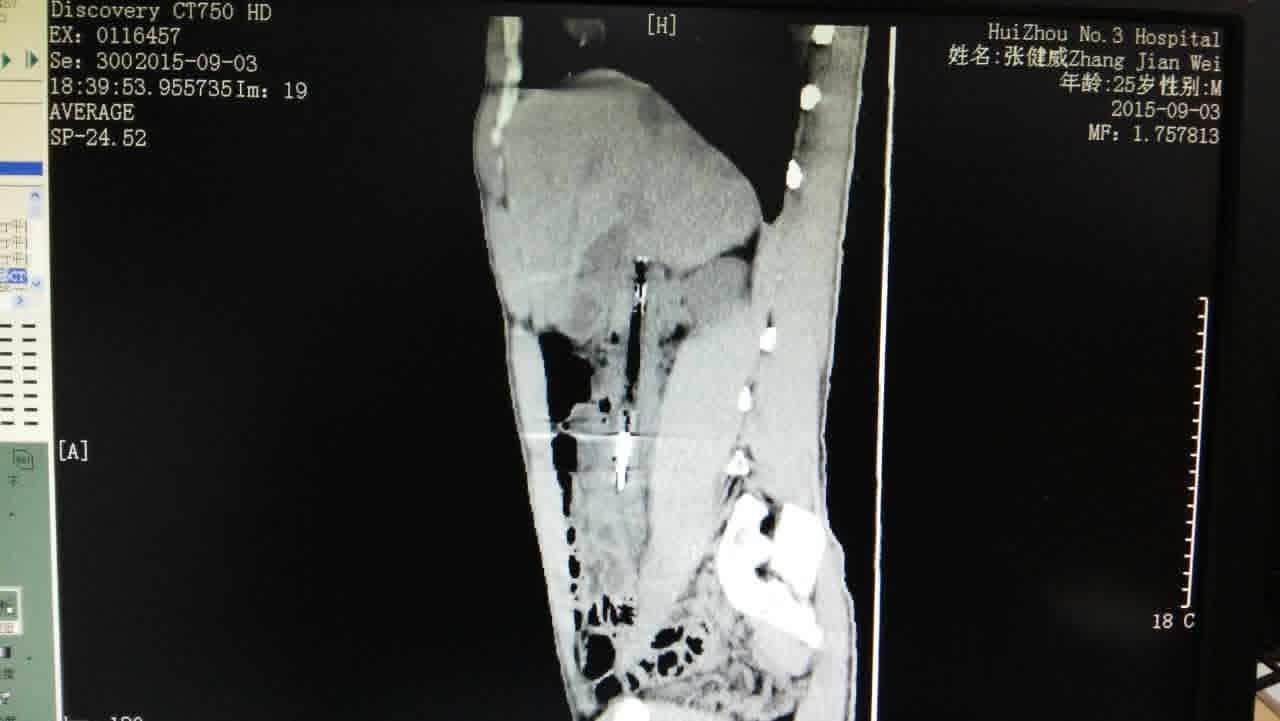

近日,我院在消化内科及普通外科的通力合作下,成功为一患者消化道异物取出。患者25岁男性,酒后吞食一“圆珠笔”,长度约15厘米,于第二天在惠州某医院行胃镜下“圆珠笔”取出术,未能成功。吞入圆珠笔第八天到我院就诊,经过消化内科及普通外科两个科室讨论,决定在手术室取异物。因“圆珠笔”已通过胃进入十二指肠并且卡的很牢固,单纯内镜下强行拉出易引起十二指肠穿孔,一旦十二指肠穿孔,处理起来比较棘手。在此情况下,普通外科医师通过腹腔镜进入腹腔,松动“圆珠笔”并往胃内方向移动,消化科医师通过胃镜就比较顺利取出这个定时炸弹“圆珠笔”。